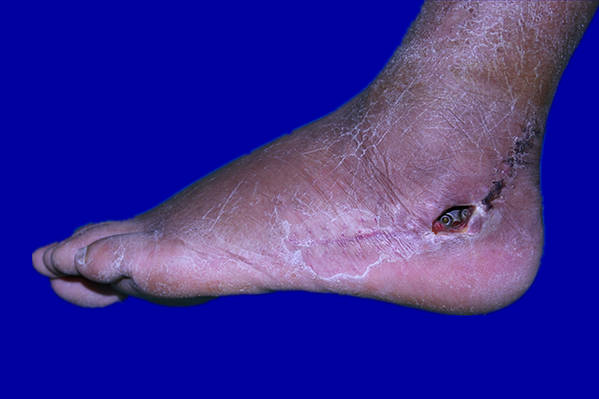

[组织瓣] 改良的外踝后穿支皮瓣修复跟骨骨折术后的皮肤缺损

术前多普勒听了,谢谢关注

外踝上2、3cm,具体按多普勒测定的位置